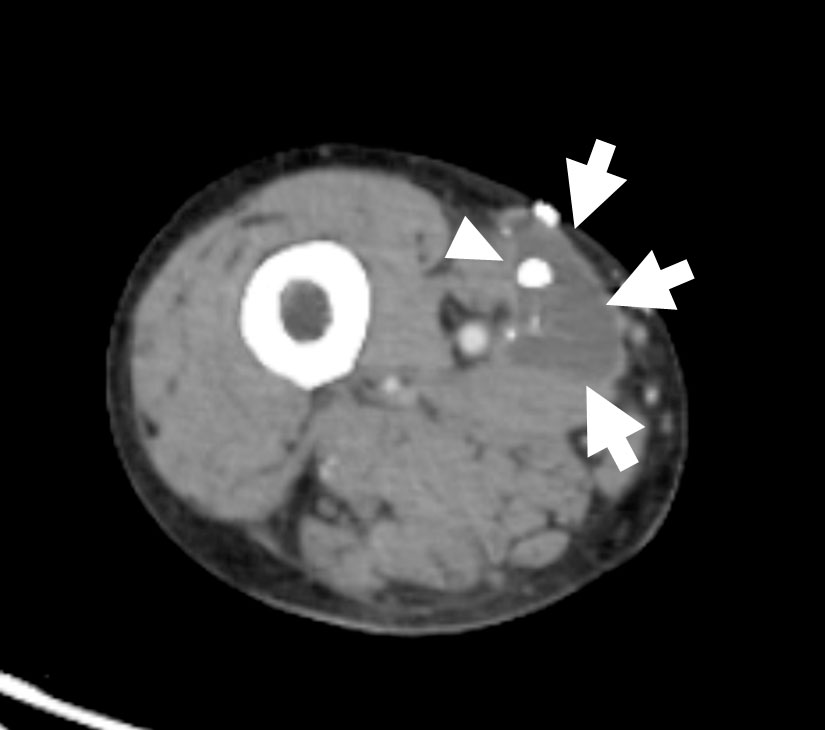

乳び胸、乳び腹水およびリンパ漏を含む、様々なリンパ液の漏出部を検出するために用いられるA Technical Review Korean J Radiol, 2014;15(6):724-732